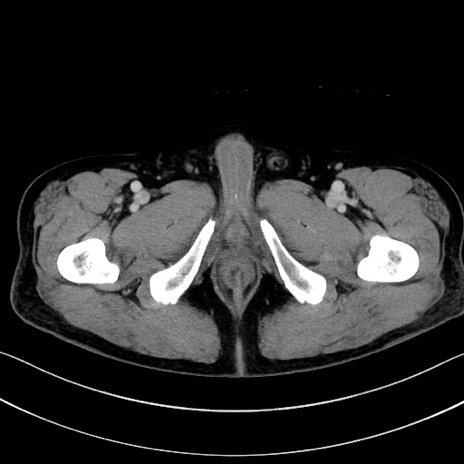

症例15(横断像)

【症例】70歳代男性

【主訴】腹痛

【現病歴】今朝から腹痛あり。全体的に痛い。特に左上の方。排ガスが今日はない。冷や汗が出る。

【既往歴】直腸癌術後

【身体所見】左側腹部〜上腹部に圧痛あり。腹膜刺激症状明らかなではない。軽度反跳痛。左下腹部に術後瘢痕あり。

【データ】WBC 7700、CRP 0.02